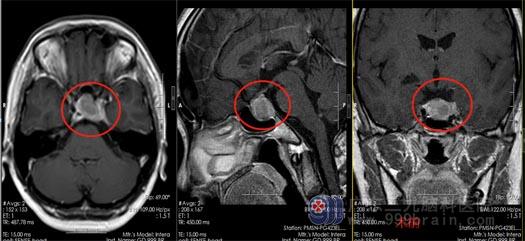

今年11月,黄女士在当地医院行头颅垂体MRI+增强检查,结果提示:鞍区占位性病变,考虑垂体大腺瘤合并卒中可能性大,检查性激素六项:泌乳素1631ng/ml,这个数据是相当的高,再参考影像检查结果,基本确定黄女士是垂体瘤导致激素分泌功能异常,引起长时间的闭经。